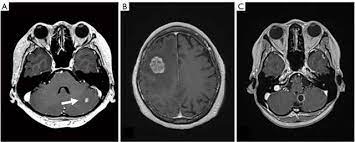

Breast Cancer Spread To The Brain Symptoms And Treatments from www.verywellhealth.com (redirected from stage iv breast cancer). Metastatic brain cancer is a mass of cells (tumor) that originated in another body organ and has spread into the brain tissue. Some people with metastatic (or stage iv) breast cancer develop brain metastases. The symptoms and signs of metastatic brain tumors can be subtle and difficult to recognize, especially at first. The incidence of brain metastasis from breast cancer (24 % in this review) is increasing due to advances in both imaging technologies leading to earlier detection of the brain metastases and introduction of novel therapies resulting in longer survival from the primary breast cancer. Metastases from breast cancer can be a frequent finding in routine oncoradiological practice. The cancer has spread to other parts of the body. Signs and symptoms of metastasis.

What you experience usually relates to where the tumor is and its size. Groaning, grimacing, or appearing restless could be signs that a. Metastatic breast cancer, also referred to as metastases, advanced breast cancer, secondary tumors, secondaries or stage iv breast cancer, is a stage of breast cancer where the breast cancer cells have spread to distant sites beyond the axillary lymph. After lung cancer, metastatic breast cancer is the second most common cancer associated with brain metastases in the united states 1. They are usually named after the tissue or organ where the cancer first developed (for example, metastatic lung or breast cancer tumors in the brain, which are the most. Systemic treatment of metastatic breast cancer. Webmd medical reference reviewed by brunilda nazario. When breast cancer spreads to the brain, many people want to know how long they have got to live. Metastases from breast cancer can be a frequent finding in routine oncoradiological practice. The symptoms and signs that people with metastatic breast cancer may experience depend on where and how much the cancer has spread. Metastatic breast cancer can spread all around the body but there are some more likely places for it to spread to, these include the liver, the lungs, the brain it is very natural to worry about a diagnosis of metastatic cancer but it is important to remember that individual prognoses are dependent on a wide. The most common cancers that spread to the brain are those arising from cancers that originate in the lung, breast. Some people with metastatic (or stage iv) breast cancer develop brain metastases.

Breast Ca 4 from case.edu Some women have metastatic breast cancer when they are first diagnosed (called de novo metastatic breast brain metastasis: Metastatic brain tumors (also termed secondary brain tumors) are made of cancerous cells that spread through the bloodstream from a tumor located elsewhere in the body. What you experience usually relates to where the tumor is and its size. Metastases from breast cancer can be a frequent finding in routine oncoradiological practice. Learn about them and when to talk to your doctor. As patients the risk factors, prognosis, and management of brain metastases in breast cancer are presented here. Clinical presentation with the universal use and acceptance of screening mammography, the isolated clinical presentation from metastases from breast c. Systematic analysis of breast cancer morphology uncovers stromal features associated with survival.